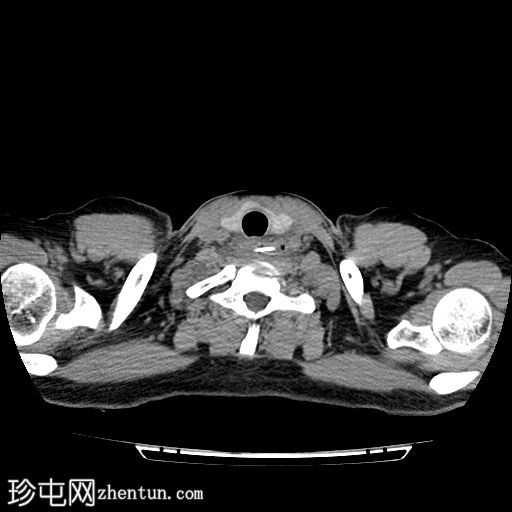

轴位

平扫

颈段食管内可见一线状水平方向的高密度异物。

颈段和上胸段食管可见长段环周强化壁增厚,符合异物嵌顿引起的反应性水肿改变。

可见食管壁撕裂,可能与异物的方向有关。此外,可见多个食管周围气腔,提示可能存在食管穿孔。

未见纵隔积气、食管周围脓肿或明显穿孔的证据。